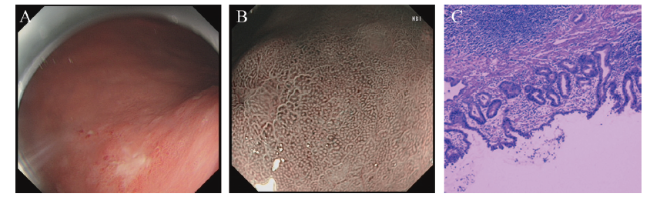

住院期间完善胸腹部CT排除转移可能,因病理活检提示胃体病灶肿瘤依据暂不充分,且与贲门下方病灶不连续,再者贲门下方病灶浸润深度为黏膜下层(SM2)可能,行ESD不一定能治愈性切除,若术中或术后提示病变进展,则需行外科手术治疗,故先行贲门下方病灶ESD。术中胃体近贲门处见片状黏膜粗糙,中央稍凹陷,NBI+ME观察腺管和微腺管不规则,边界欠清,病变大小约6.4 cm×6.0 cm(图2A、B)。ESD术后病理示“胃体近贲门ESD标本”腺癌(图2C)。肉眼类型:0-Ⅱb+Ⅱc;病变范围:1.6 cm×1.1 cm;组织学类型:腺癌(tub1 > pap > tub2);浸润深度:黏膜下层(SM1);溃疡瘢痕(-);脉管侵犯(-);切缘:水平切缘(-)、垂直切缘(-)。周围黏膜示轻度慢性萎缩性胃炎伴轻度肠化伴淋巴滤泡增生。免疫组织化学(组化)染色结果示癌组织Desmin(平滑肌+)、SMA(平滑肌+)、CD31(内皮细胞+)、D2-40(淋巴管+)、Ki-67(50%+)、p53(90%+)、MLH1(+)、PMS2(+)、MSH2(+)、MSH6(+)、HER-2(-)、MUC-2(+)、MUC5AC(-)、MUC-6 (部分+)。弹力纤维特殊染色示脉管壁完整。患者贲门下方病灶治愈性切除,而胃体病灶为LGIN,且内镜下有明显的病灶及清晰的边界,有ESD指征,故嘱患者3个月后回院治疗。患者第2次ESD中见胃体小弯侧黏膜粗糙,局限黏膜隆起,中央稍凹陷,NBI+ME观察腺管不规则,局部血管延长、扭曲(图3A、B)。病变大小约5.0 cm×5.5 cm。术后病理示“胃体小弯ESD标本”腺癌(图3C);合并GCP伴部分上皮HGIN。肉眼类型:Ⅱc+Ⅱa;病变范围:3.0 cm×2.2 cm;组织学类型:tub1 > pap > tub2;浸润深度:黏膜下层(SM1);溃疡瘢痕:(-);脉管侵犯:(-);切缘情况:侧切缘(-);基底切缘(-)。周围黏膜示重度慢性萎缩性胃炎伴重度肠化及GCP。Hp(-)。免疫组化染色结果示p53(50%+)、Ki-67(40%+)、Desmin(肌+);p53(60%+)、Ki-67(60%+)、Desmin(肌+);p53(50%+)、Ki-67(40%+)、Desmin(肌+);p53(80%+)、Ki-67(50%+)、MUC5AC(+)、MUC-6(+)、Desmin(肌+)、CD34(血管+)、D2-40(淋巴管+)。最后诊断:SMPEGC。预后情况:患者ESD术后3个月、术后1年分别于我院复查胃镜及胸腹部CT未见明显复发转移征象。

图3 一例SMPEGC合并GCP患者第2次胃体小弯ESD治疗及病理图

注:A为胃体近贲门病变术后改变;B为胃体小弯的白光改变;C为胃体小弯的NBI+ME图;D为胃体小弯ESD术后病理(HE染色,×200)。